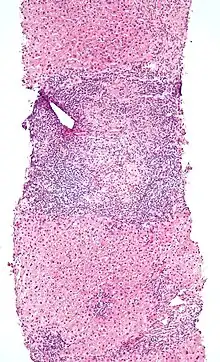

Micrograph of PBC showing bile duct inflammation and injury.

Low magnification micrograph of PBC. H&E stain.

On microscopic examination of liver biopsy specimens, PBC is characterized by chronic, non-suppurative inflammation, which surrounds and destroys interlobular and septal bile ducts. These histopathologic findings in primary biliary cholangitis include the following:[34]

- Inflammation of the bile ducts, characterized by intraepithelial lymphocytes, and

- Periductal epithelioid granulomata.

- Proliferation of bile ductules

- Fibrosis (scarring)

The Ludwig and Scheuer scoring systems have historically been used to stratify four (1–4) ‘stages’ of PBC, with stage 4 indicating the presence of cirrhosis. In the new system of Nakanuma, the stage of disease is based on fibrosis, bile duct loss and features of cholate-stasis, i.e. deposition of orcein-positive granules, whereas the grade of necroinflammatory activity is based on cholangitis and interface hepatitis. The accumulation of orcein-positive granules occurs evenly across the PBC liver, which means that staging using the Nakanuma system is more reliable regarding sampling variability.